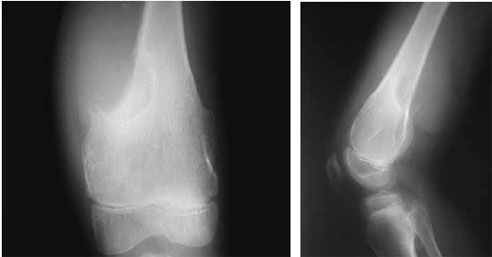

Raio-x

Sinais de rarefação e lise óssea: lesões osteolíticas

Reação periosteal: espessamento ou ruptura da linha do periósteo.

Triângulo de Codman.